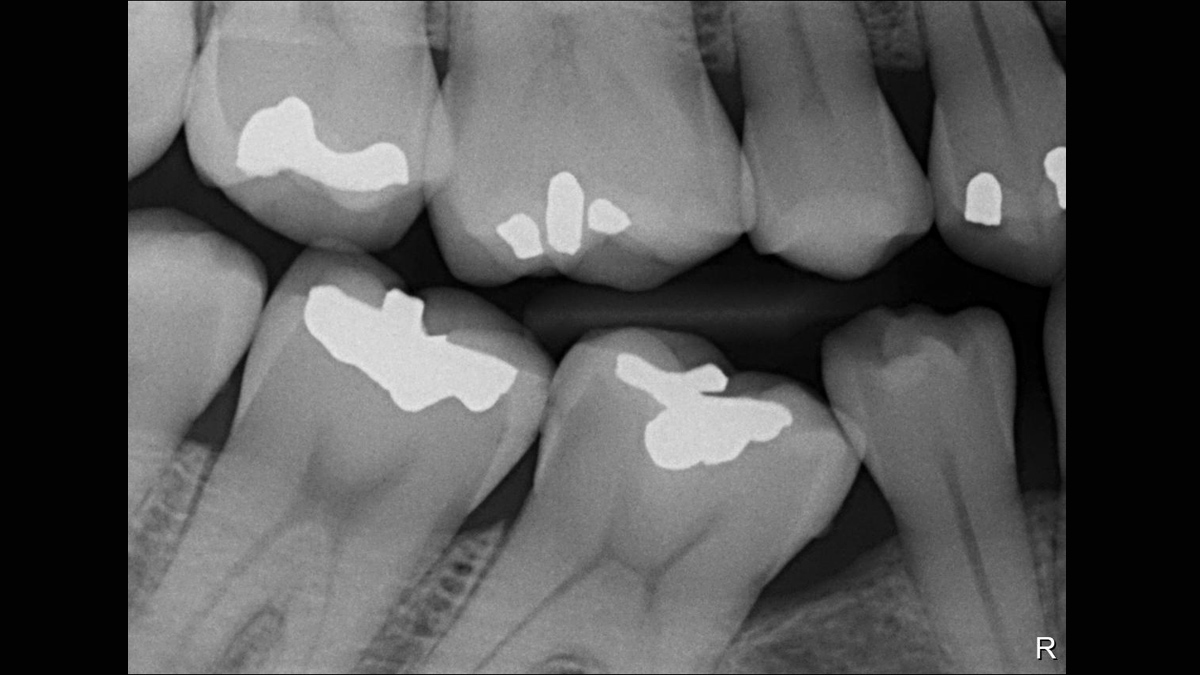

Éles, részletes képminőség, ami nem hasonlítható össze más digitális szenzorral. Az intraorális szenzor páratlan tisztaságot, élességet és részletességet biztosít a digitális radiográfiához.

A kiemelkedő képfelbontás elengedhetetlen az élek meghatározásához, a káriesz és más hibák azonosításához. A 33 lp/mm elméleti felbontás mellett a Xios XG Supreme az iparág vezető felbontását és minőségét kínálja.